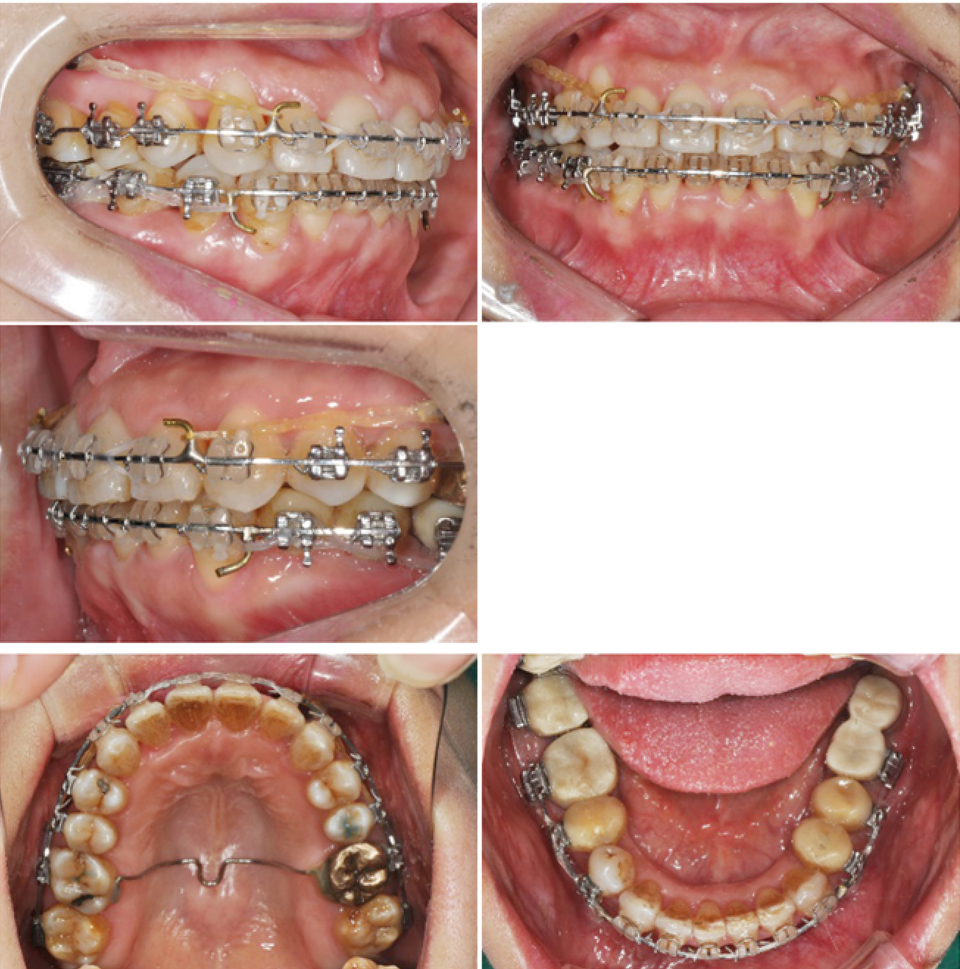

상악에서 miniscrew를 이용한 2mm 정도의 total arch distalization을 계획하였으므로 상응하는 최종교합형성을 고려하여 하악 대구치부에 임플란트식립을 진행하였고 구치부 support의 조기확립을 위해 temporary crown을 이용한 임플란트 상부보철 진행후 하악치열의 후방이동을 진행하기로 하였습니다.

하악임플란트상부보철물에 tube를 부착하되 tube slot에 각형호선이 가급적 passive 하게 들어가도록 보철물의 모양과 tube 부착위치를 조절하였습니다. 계획된 후방이동량만큼 임플란트 보철물과 전방 자연치간의 space를 형성하여 전방치열을 후방견인하였습니다.

마무리된 교합은 초진시에 동일하게 양측 Class 1 교합으로 마무리하였으며 측모두 부방사선 사진에서 보듯 교정중 발생했던 전치의 flare가 개선되었습니다.